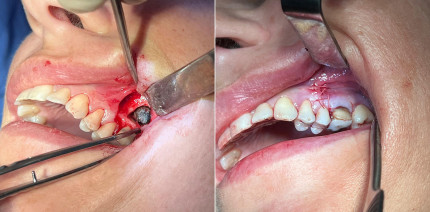

Fungusball in der Kieferhöhle nach Wurzelkanalbehandlung